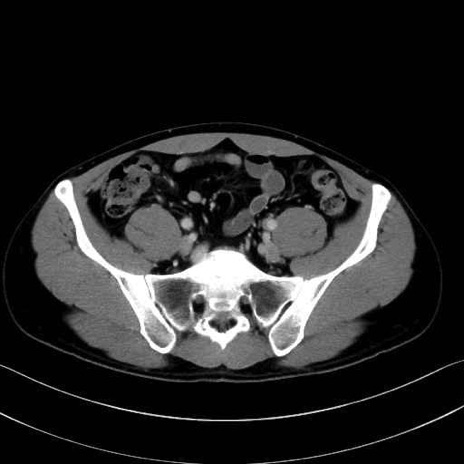

梨状筋(piriformis muscle) のCT画像の解剖

梨状筋 (Piriformis)

内閉鎖筋 (Obturator internus)